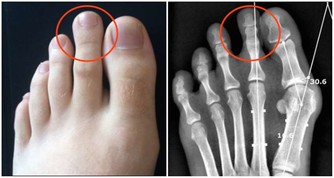

18. 忍痛力降低

已經有研究顯示,

若晚上睡眠不足,

人體對於疼痛的敏感度會提高,同時對於疼痛的忍受力則會降低。